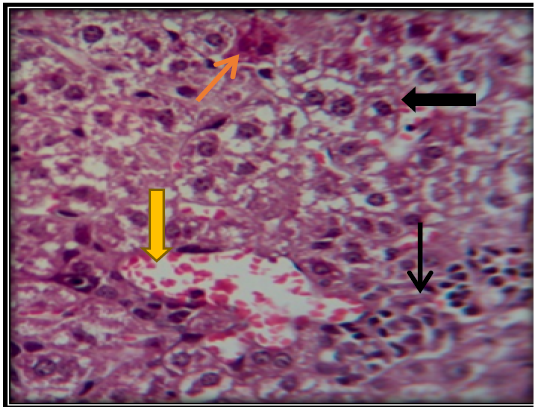

Liver section for mouse treated with AFB1showing congestion of central vein ( ) with vacuolation of hepatocyte ( ) and apoptotic cells ( ) and accumulation of inflammatory cells in necrotic areas ( ) (H&E 200X).